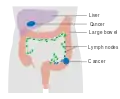

Dukes stage C bowel cancer; the cancer has invaded the nearby lymph nodes. Dukes stage D bowel cancer; the cancer has metastasized.

Dukes stage D bowel cancer; the cancer has metastasized.